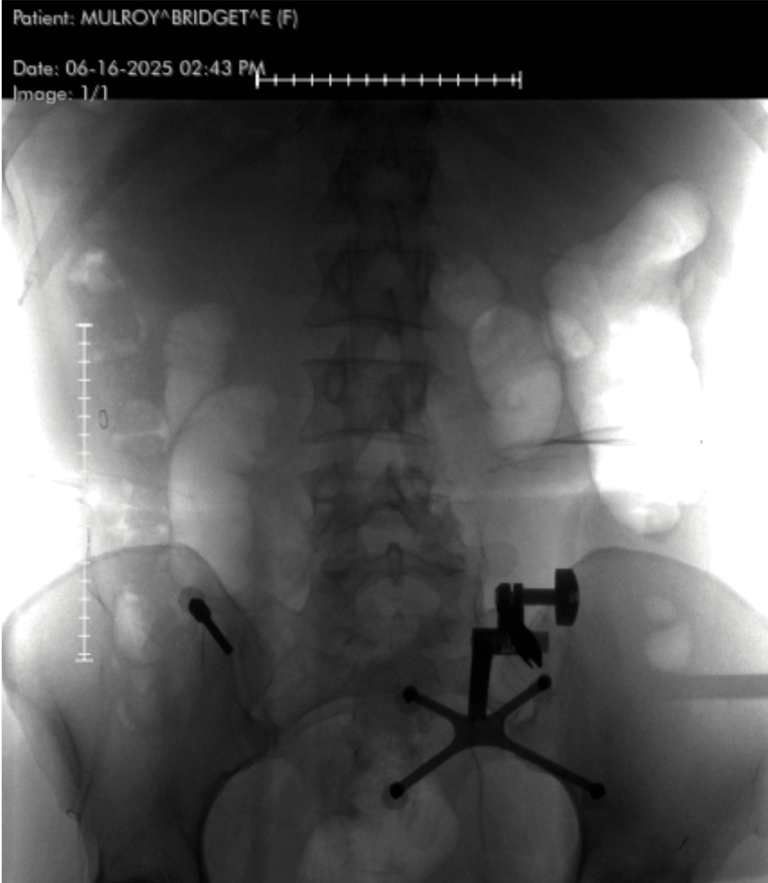

Image Credit: Bridget Mulroy

He performed a minimally invasive posterior lumbar instrumentation from L2 to L5. That means he made small incisions guided by real-time navigation using a machine called the O-arm—a rotating intraoperative CT scanner. A localizing pin in my pelvis communicated with a computer, which told him exactly where to place each screw.

“Once the screws are inserted,” he explained, “I use an X-ray to place the rods. The key decisions involve knowing which levels to include, ensuring screw trajectory is perfect, and having a plan if something doesn’t go right.”

“The process behind a posterior instrumentation with stabilization is as follows (I did this minimally invasive so it’s slightly different): I placed a metal localizing pin into your pelvis which talks to the computer in the room which helps us with real time screw navigation. We spin a large machine called an O-arm which performs in intraoperative CT scan which gives us a lot of information about your bones. We use that as a real time navigation for placing the screws into the bones. We then used a special marker to know exactly where to place your incisions based on the real-time feedback from the navigation (we can keep the multiple incisions small because of this technology). Once the incisions are made, we dissect down the skin, fascia, muscle, and down to the bones of the spine. From there I use the real-time navigation to understand the trajectory of the screw and place each one with a set of instruments—first an awl to make a small hole in the bone, then a tap to widen that hole a bit in order to better facilitate screw insertion, then the actual screws. Once the screws are inserted, I use an x-ray machine to help me place the rods. The real decision making here includes the pre-operative planning and knowing which levels to include, the proper screw trajectory and to know if the feedback from the live navigation is accurate, and what to do if a screw isn’t perfect.”